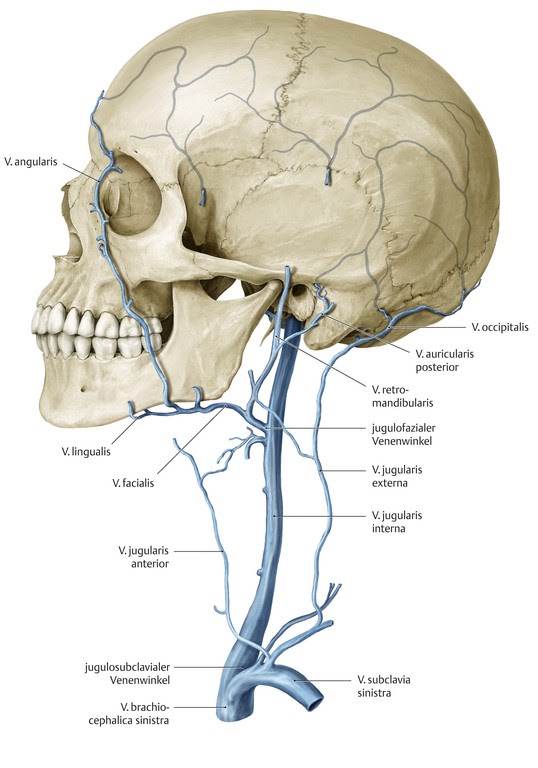

Анатомия внутренней яремной вены: КТ изображения